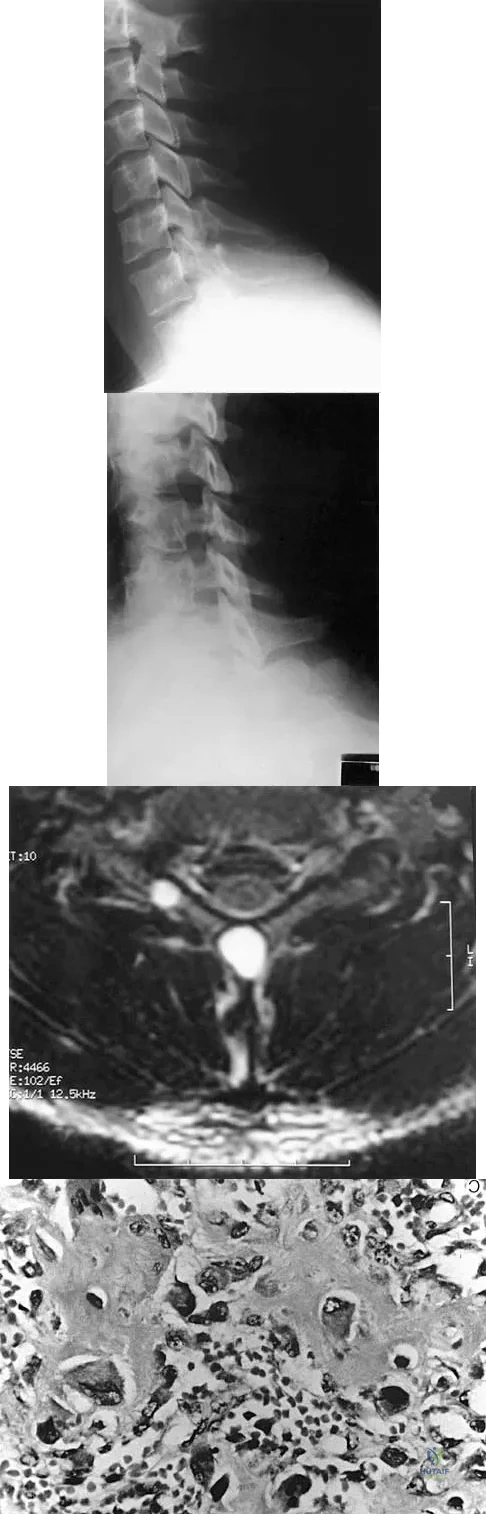

A 45-year-old man seen in the emergency department reports a 1-week history of worsening low back pain and a progressive neurologic deficit in the S1 distribution. Examination reveals 2/5 strength in the gastrocnemius. Laboratory studies show a WBC count of 13,500/mm3 and an erythrocyte sedimentation rate of 74 mm/h. Radiographs of the lumbosacral spine show narrowing of the L5-S1 disk space, with irregularity of the end plates. A sagittal T2-weighted MRI scan is shown in Figure 8. Definitive management should consist of

A 19-year-old man has had back pain with activity, especially running in soccer and baseball, for the past 4 months. He denies any history of trauma. Examination reveals no motor weakness or sensory changes in the lower extremities. Range of motion shows increased pain with extension and mild limitation with flexion. A sitting straight leg raising test is limited at approximately 60 degrees bilaterally by back and buttocks pain. Plain radiographs are normal. MRI scans are shown in Figures 13a through 13e. What is the most likely diagnosis?

A 24-year-old man sustains the injury shown in Figures 19a through 19e in a paragliding accident. He is neurologically intact. He also sustained fractures of his left femur and right distal radius. Which of the following represents the best option for management of the spinal injury?